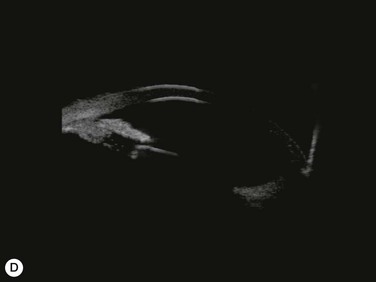

Substantial increases in anterior chamber depth and angle width following cataract extraction with intraocular lens (IOL) implantation have been demonstrated in eyes with PAC (Fig. 108-2A,B).23–25 The narrower the preoperative anterior chamber angle, the greater the alteration of angle configuration. Whereas iridolenticular contact was observed in a phakic eye, there was no iris and IOL contact in a pseudophakic one (Fig. 108-2A,B). The iris plane shifted backward, deepening the central anterior chamber by approximately 850 µm. Preoperative biometry performed in a series of 52 eyes of 48 consecutive Thai middle-aged patients who had developed acute PAC within 6 months showed that average natural lens thickness and central anterior chamber depth were 4.83 mm and 1.8 mm, respectively.26 Since the IOL (PMMA, silicone, acrylic) thickness in the 20–25 D power ranges from 0.75 mm to 1.42 mm. Replacement of the natural lens with the IOL provided up to 4 mm more axial distance within the anterior segment eliminating angle crowding and appositional closure. In addition, anterior chamber deepening with a viscoelastic during IOL implantation might break recent PAS.

Several studies have shown that extracapsular cataract extraction (ECCE) with IOL implantation is effective in opening the angle and controlling IOP in refractory PAC.27–30 Currently, ECCE has been replaced by phacoemulsification which offers a higher surgical success rate, less postoperative inflammation and fewer complications. In addition, the clear corneal approach spares the superior conjunctiva for possible filtering surgery, if needed. Phacoemulsification and IOL implantation has been reported to be highly effective in patients with uncontrolled PAC.31,32 However, up to 32% of the patients still had persistent PAS and required long-term treatment with glaucoma medication following lens removal either by ECCE or phacoemulsification and IOL implantation alone (Fig. 108-2A).5,32 Goniosynechialysis is the next step to eliminate the remaining synechiae and control the IOP (Fig. 108-2C).

Goniosynechialysis becomes more effective when performed after lens removal. An increase in the anterior chamber space provides ample room to perform the procedure and reduces the chance of synechial reformation. Combined phacoemulsification and GSL (phaco-GSL) has been shown to be safe and highly effective in controlling IOP (<21 mmHg) and decreasing PAS in >90% of 52 eyes that developed acute PAC within 6 months and had persistent IOP elevation following laser treatment.26,33,34 Postoperative IOP was reduced to below mid-teens regardless of the preoperative IOP level. Recurrence of the PAS, although uncommon, might occur during the first three months. The success of phaco-GSL has been stable since the third postoperative month for up to 14 years, providing a long-lasting control or even a permanent cure.26 A recent multicenter study also demonstrates a success rate (< 21 mmHg) of 85.9% in 109 eyes with uncontrolled PAC/PACG at one and three years following phaco-GSL.35

Patients are treated with antiglaucoma medications and frequent topical steroids. When the inflammation subsides, the medications are then slowly tapered off within a month. Occasionally, a release of aqueous through the paracenteses at the slit lamp may be performed if a high IOP rise occurs. Gonioscopy typically reveals opening of the angle structures with irregular pigmentation on the newly exposed trabecular meshwork and the angle wall (Fig. 108-6). Angle recession or a cyclodialysis cleft are undesirable findings. If successful, anterior segment optical coherence tomography or ultrasound biomicroscopy should demonstrate separation of the PAS and reopening more than half of the entire angle (Figs 108-2, 108-7).